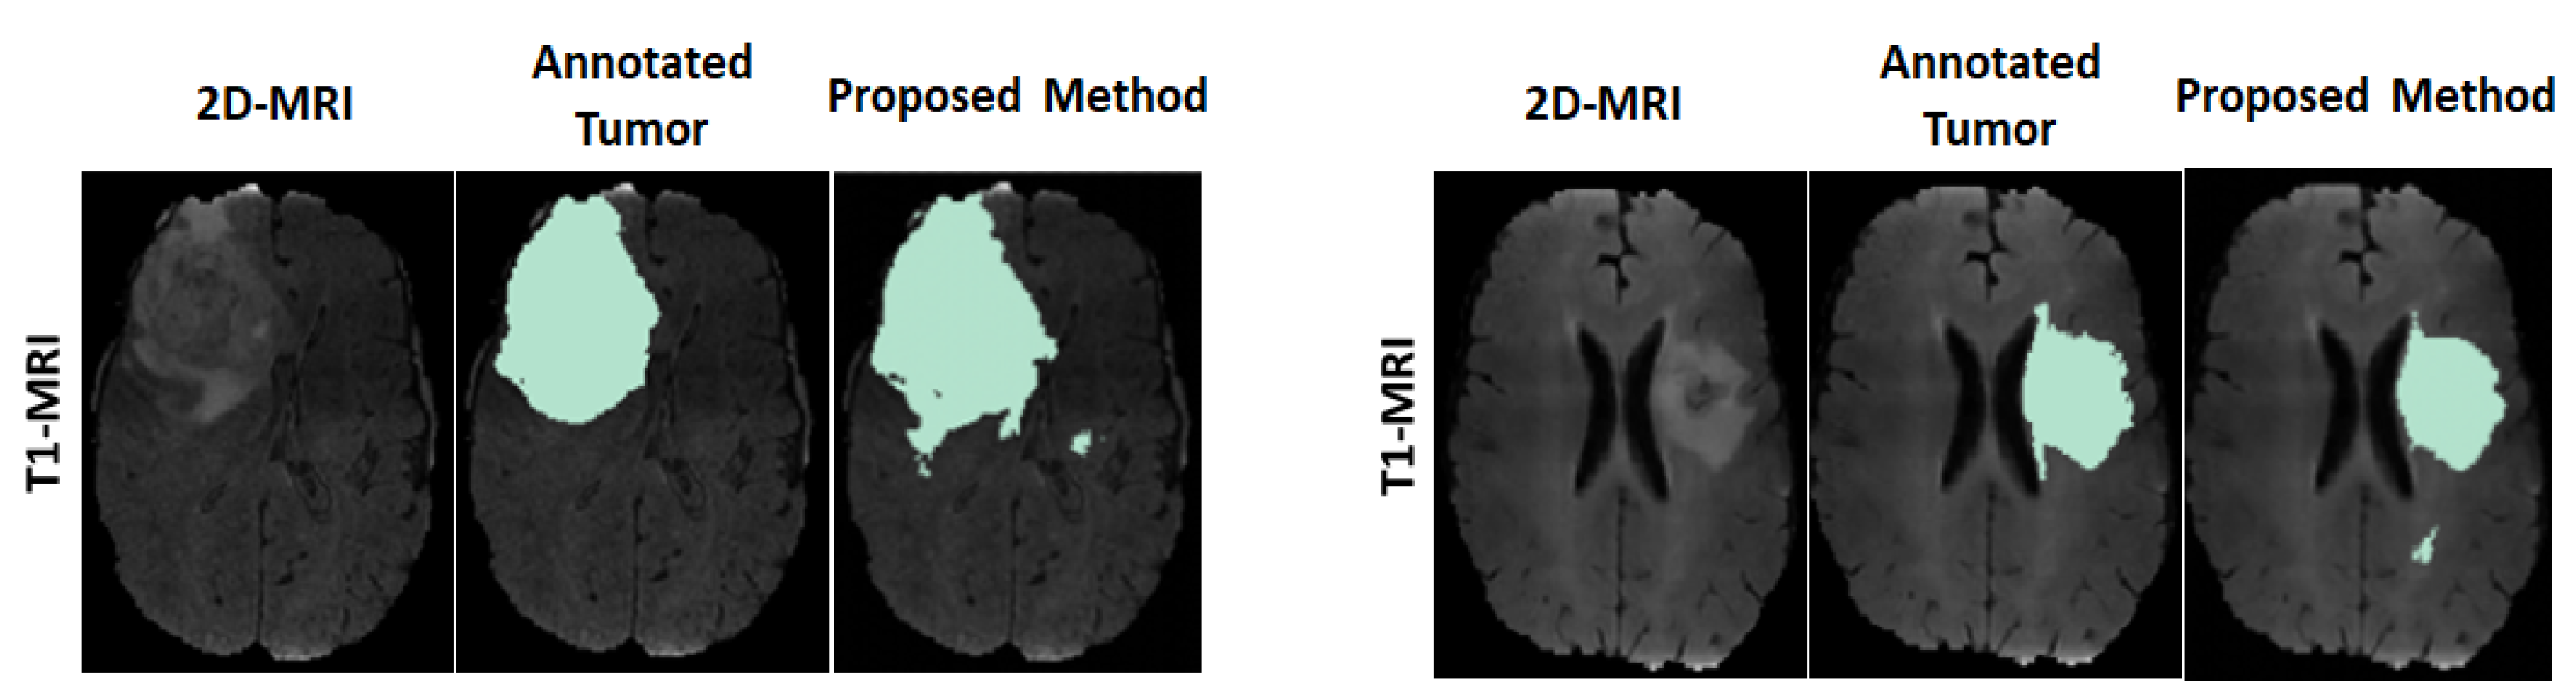

For visual observation on the segmented tumors, Figure 4 shows an example of two segmented tumor images (column 3 on left and right) by using the proposed approach.

Figure 4. Example of two segmented brain tumor images from the MICCAI test set. Columns (on left and right): original T1 MR image; annotated tumor area marked by medical experts; segmented tumor area from proposed method.